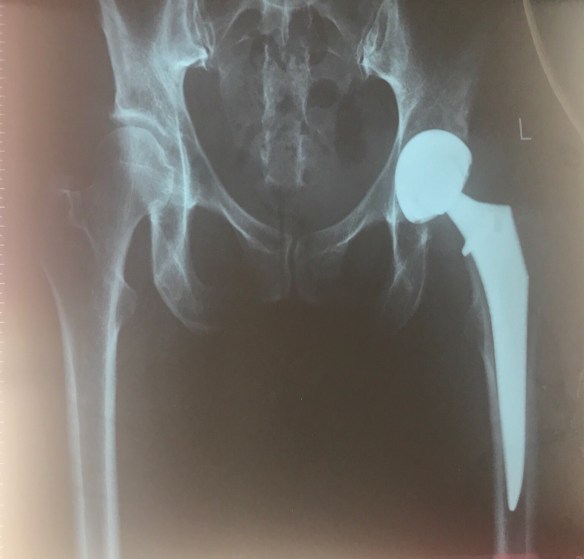

I donโt have any scales to weigh in which is a shame however I would like to get a few good weeks of healthy eating and exercise under my belt before I weigh again. Iโm back in the gym in the afternoon when they open at 5 pm for another 30 minutes of cardio. I have split the cardio into two 30 minute sessions as I find that my left knee can sometimes exhibit some referred pain from the hip operation so just need to take it easy until the strength in my muscles is rebuilt.

Friday morning is chest and shoulders โ shoulder press, shoulder shrugs, lateral and front raises, push ups, scarecrows and rear delt followed by 30 minutes on the cross trainer. I am beginning to feel more normal โ I probably feel the best I have since prior to my operation so am really looking forward to some serious training in the next few weeks.

Today is my 6 week anniversary since having the hip operation and so I will now sign off Hippy Times. The next blog phase will take us through May to early June when David and I go to the UK so join me on Wednesday morning to discover the next challenge!